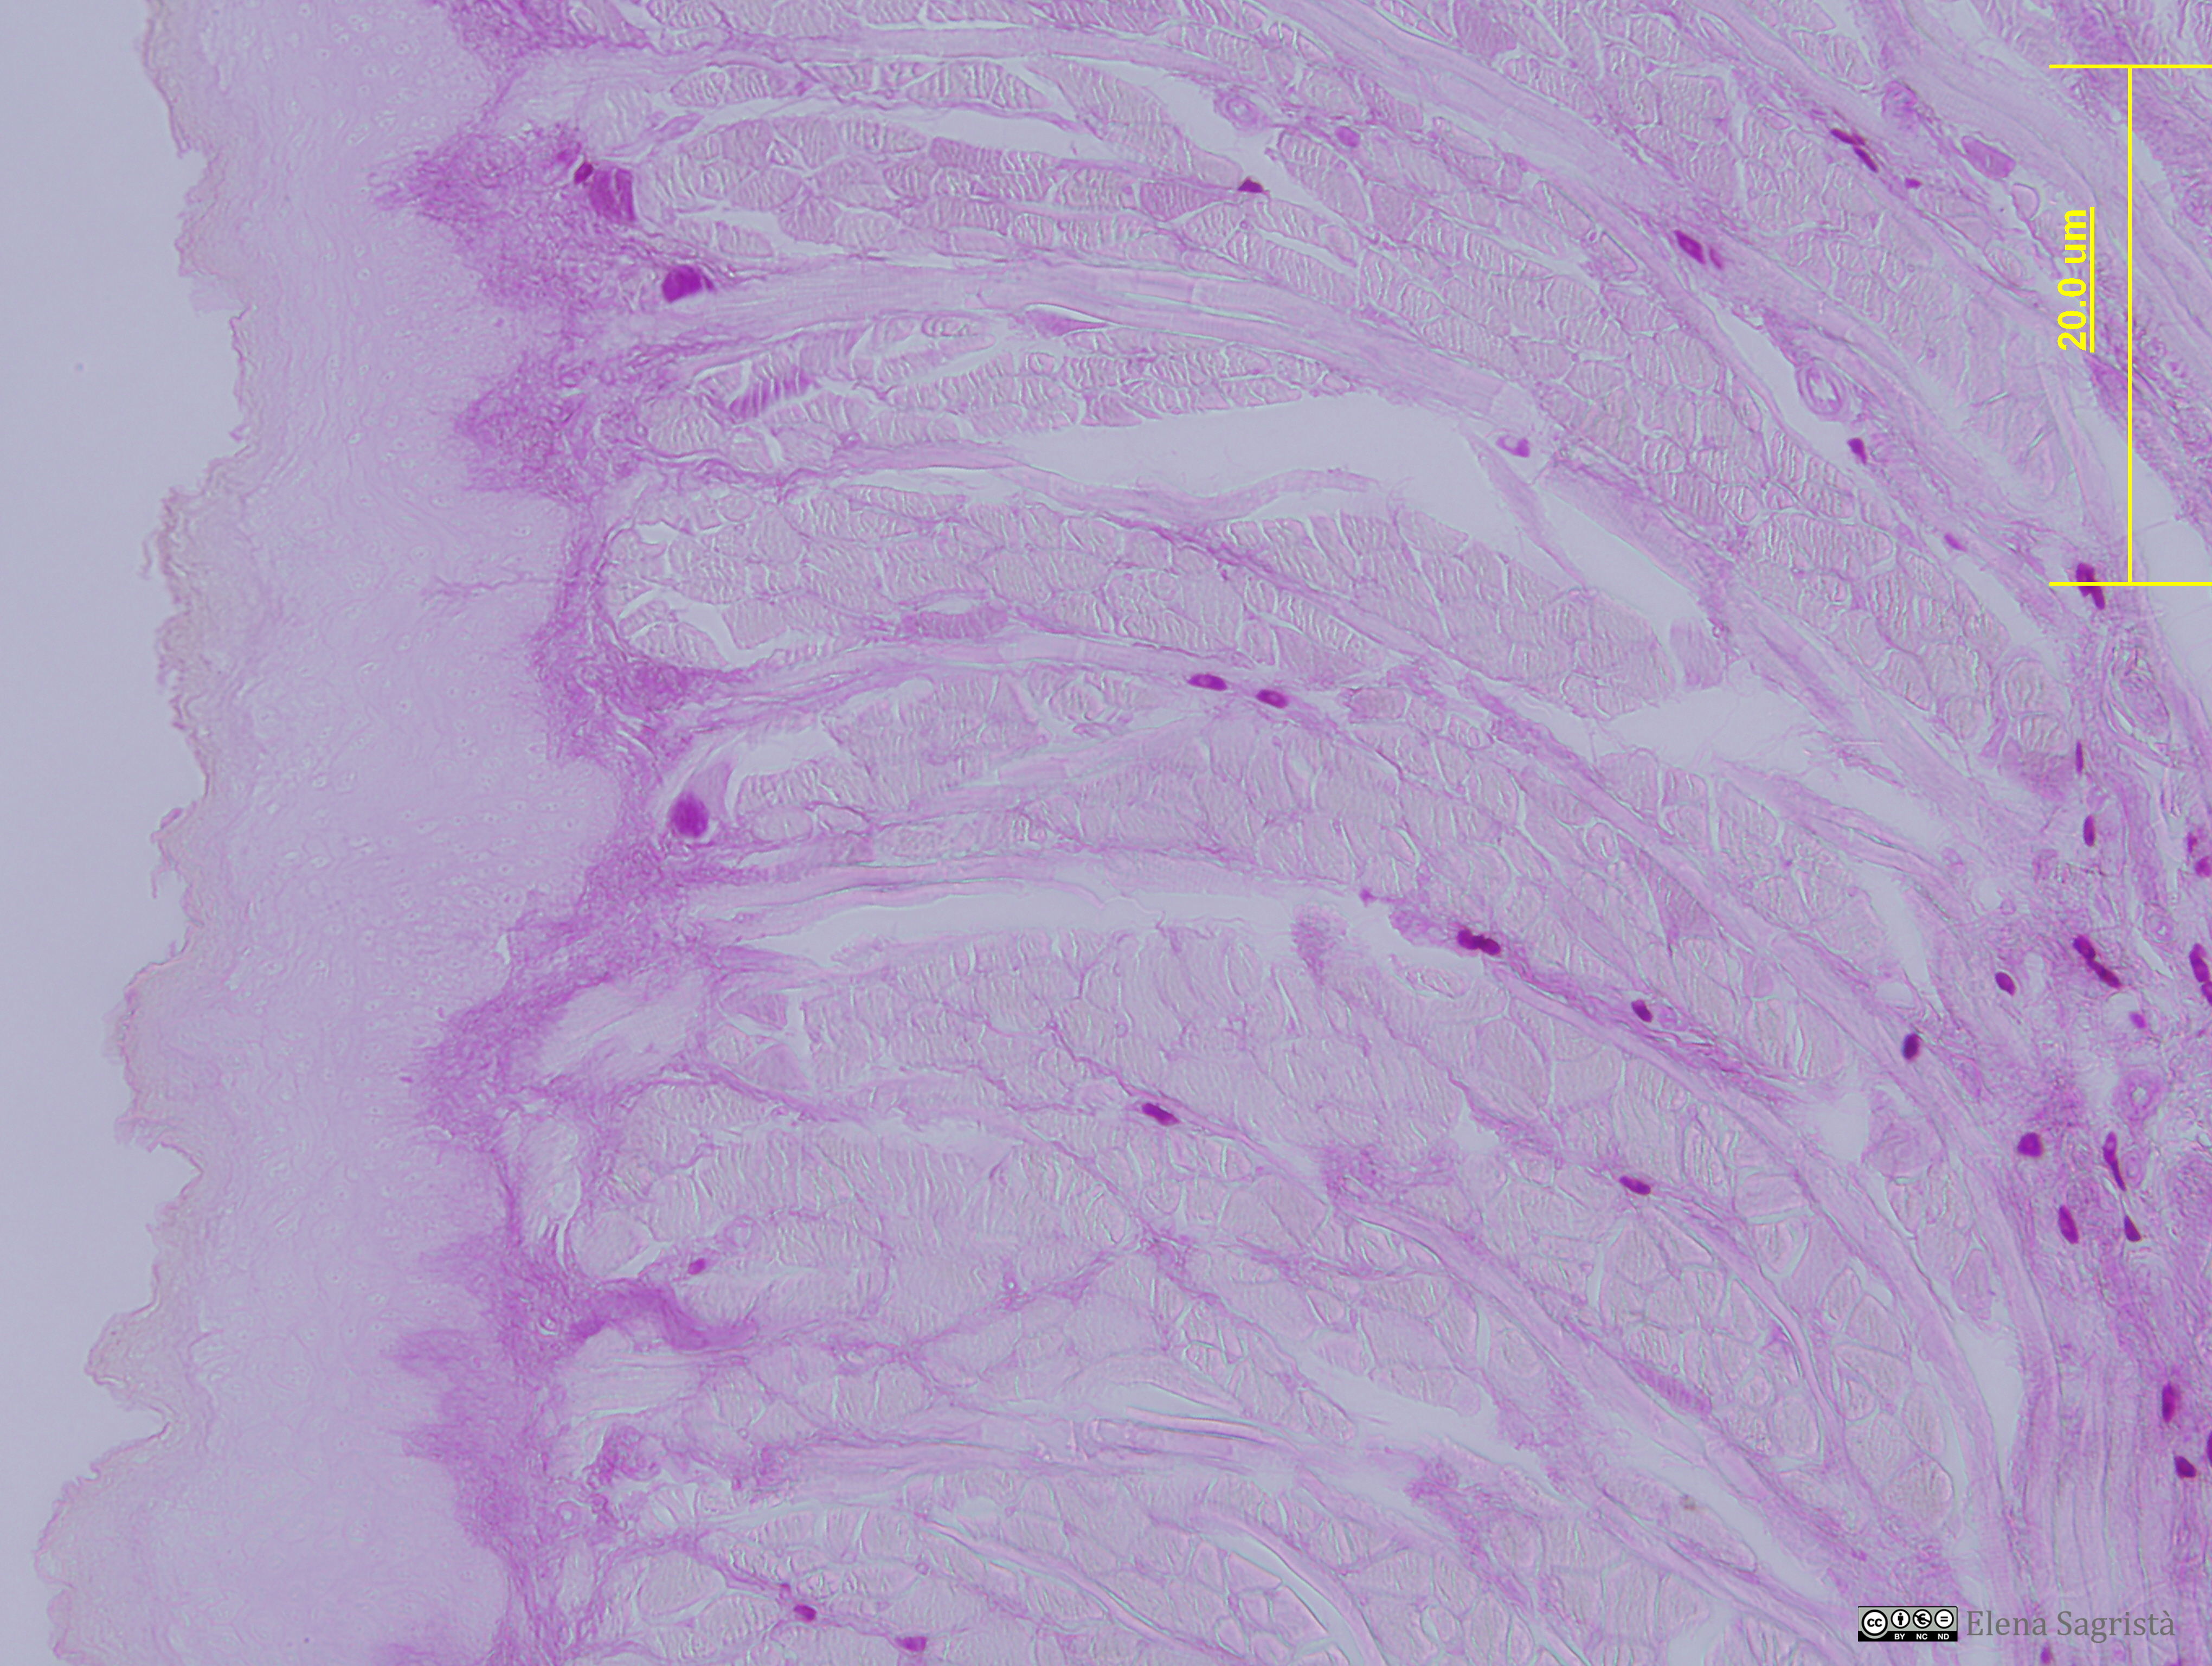

Histologia imatges: 02 Teixit conjuntiu

Imatges de preparacions histològiques de Teixit conjuntiu. Microscopia òptica.